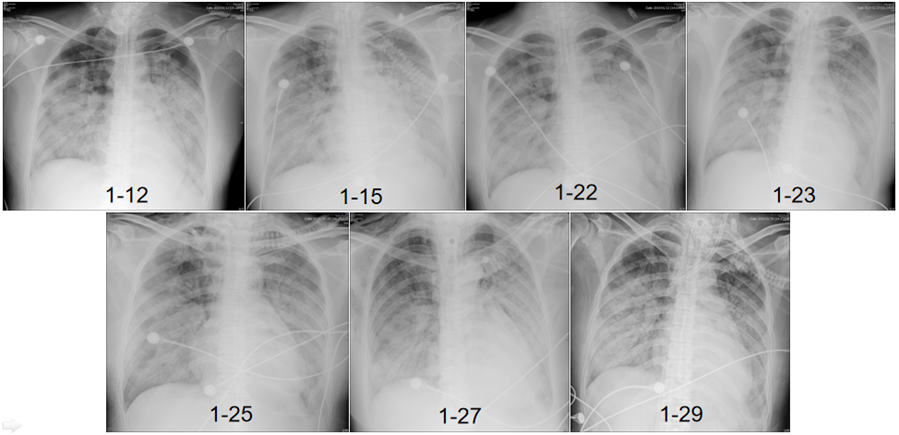

调整方案治疗后,2月2日患者有好转趋势,但在2月4日,由于患者右肺发生气胸(活检在左肺),且出现反复的高危肺栓塞(图8),最终未能抢救成功。